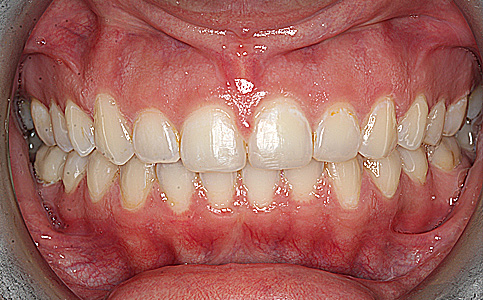

Pierwszym etapem była deprogramacja zgryzu i wyleczenie ubytków próchnicowych, następnie ustabilizowanie nowej pozycji szczęki względem żuchwy i poprawa estetyki zebów z tego powodu założone zostały korony pełnoceramiczne.

Zobacz efekty przeciągając suwak w prawo lub w lewo.